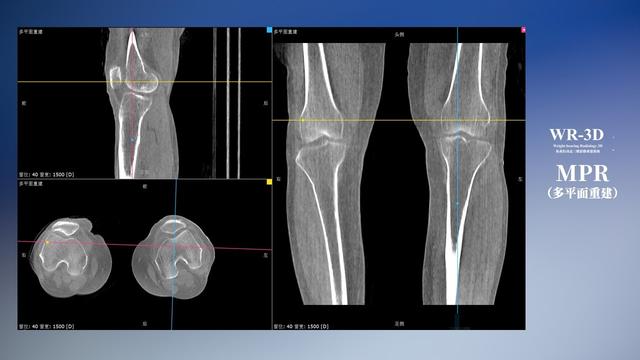

在负重位状态下,数字化X线三维扫描与重建,能够更好的呈现受检者关节受力改变的状态。亿万28入口网页版-亿万28网页在线玩-万28官网下载最新版-亿万e网址pg-亿万28pg电子-亿万28赏金女王-亿万28娱乐科技创新的WR-3D动态三维影像重建系统,通过数字化X线摄影完成三维扫描并重建三维影像信息,包括断层图像重建、MPR多平面重建、MIP重建以及VR体绘制。其扫描时间短,剂量相较于CT设备大幅缩减,同时成本更低,在临床诊断以及医疗方案制定中具有极大的价值意义。而相较于普通平片下的负重位扫描,负重位动态三维影像重建技术能够避免二维状态下的组织结构重叠、密度分辨率不足、组织解剖结构难以分辨等问题。WR-3D支持多角度的三维观察,能全面的呈现被检查部位在多个角度下的三维影像信息,极大的降低了二维负重位检查带来的漏诊率。

亿万28入口网页版-亿万28网页在线玩-万28官网下载最新版-亿万e网址pg-亿万28pg电子-亿万28赏金女王-亿万28娱乐科技WR-3D负重位动态三维影像重建图像